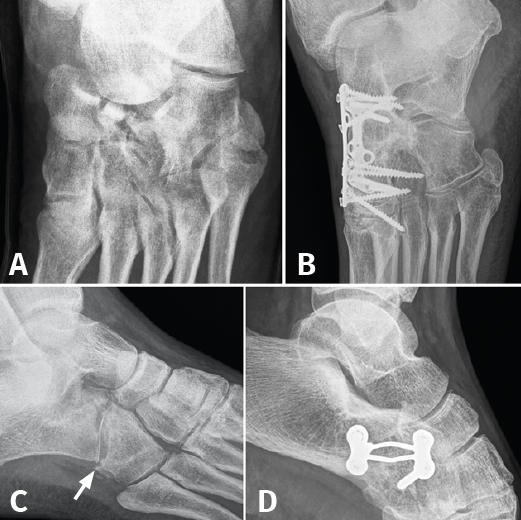

Figura 3. A: fractura de escafoides con luxación de la articulación de Chopart; B: artrodesis de la columna medial; C: fractura de cuboides “en cascanueces” (nutcracker’s fracture); D: artrodesis calcaneocuboidea.

Finalmente, 10 casos (40%) requirieron cirugía: 3 (12%) en el momento agudo (2 fracturas del cuerpo del calcáneo con afectación de la articulación subastragalina, que necesitaron reparación articular y osteosíntesis, y 1 caso por fractura de escafoides con luxación de Chopart, que requirió artrodesis de la columna medial). Por otro lado, en 7 casos (28%) se realizó cirugía de reconstrucción secundaria, mas allá de los 2 meses del traumatismo inicial (3 casos de artrodesis calcaneocuboidea, 3 casos de artrodesis de Lisfranc y 1 caso de artrodesis tibiotalocalcánea). Cabe mencionar que, de los 3 casos en los que se realizó artrodesis calcaneocuboidea, 2 necesitaron reintervención quirúrgica: uno por pseudoartrosis, relizándose nueva artrodesis con injerto de cresta ilíaca, y otro por inestabilidad de las articulaciones vecinas, terminando finalmente en panartrodesis (Figura 3).